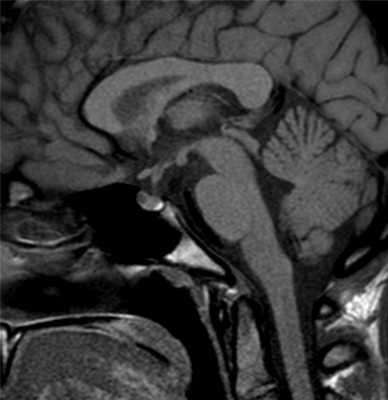

МРТ гипофиза в норме

В норме воронка гипофиза должна располагаться на срединной линии, а сама железа - иметь однородную структуру и близкую к прямоугольной форму. Его нижний край должен напоминать изгиб турецкого седла, а верхний может быть выпуклым, прямым или вогнутым. На фронтальной проекции его части должны быть симметричны, но легкие отклонения не считаются патологией.

Нормальное МРТ гипофиза показывает отсутствие отклонений в его величине и структуре. Нормальными показателями для взрослого человека средней комплекции считаются:

- ширина - 6—8 мм;

- длина - 5—13 мм;

- высота - 3—5 мм.

В период физиологических гормональных колебаний (во время беременности или в пубертатном возрасте) эти показатели могут незначительно колебаться, что не является признаком патологии. Но если любой из этих параметром превышает 10 мм, это является признаком микроаденомы. Особое внимание при магнитно-резонансной томографии области турецкого седла уделяется показателям высоты гипофиза, поскольку другие изменяются значительно реже.